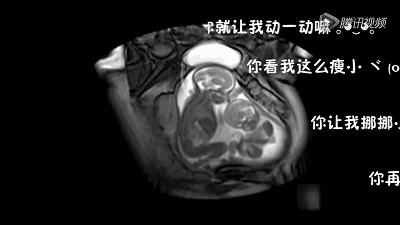

胎寶寶在媽媽肚子裡,就好比小魚在水裡,靈活的很。大動作翻身,打挺之類的,小動作吃手指,皺眉頭都有。一起來看看下面這張圖,看看胎寶寶都在做些什麼運動吧。